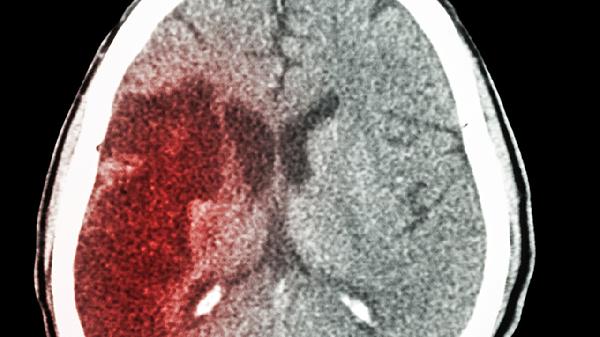

脑出血后遗留的手脚麻木属于中枢性感觉障碍,主要因出血灶压迫或破坏感觉传导通路所致。珍宝丸作为中成药,含人工麝香、珍珠、牛黄等成分,具有活血化瘀、通络止痛作用,可能通过改善局部微循环辅助缓解麻木感,但对已受损的神经结构无修复作用。临床更常使用甲钴胺片、维生素B1片等营养神经药物促进功能恢复,或依达拉奉注射液减轻氧化应激损伤。